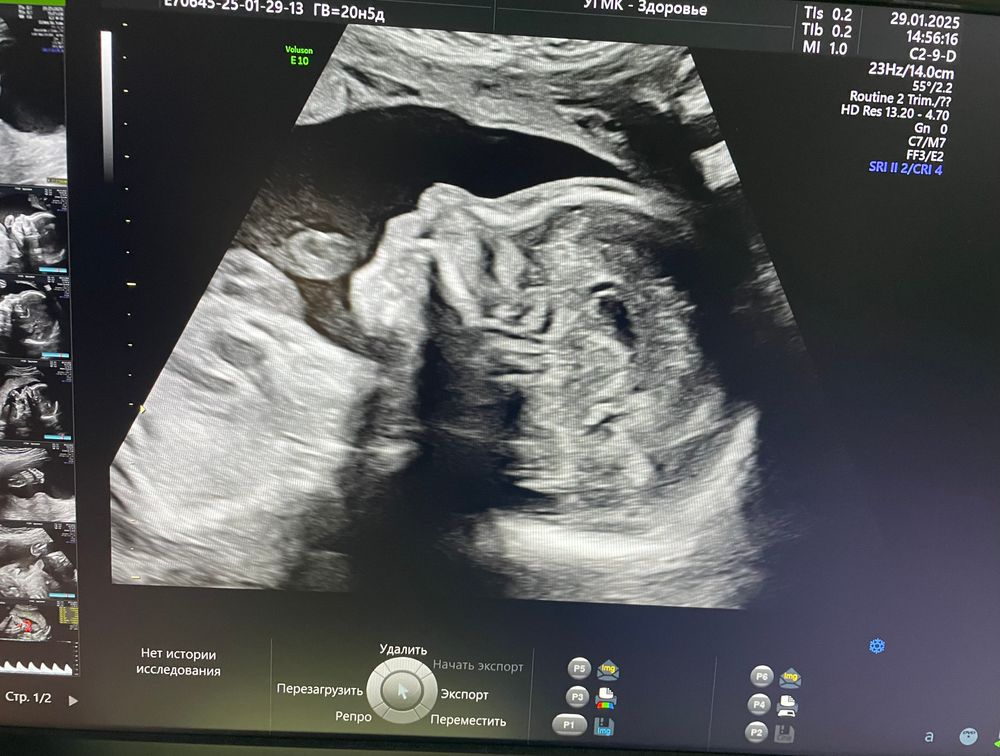

Как приятно смотреть на этого малыша) люблю его 👼

Срок 20,4 недели